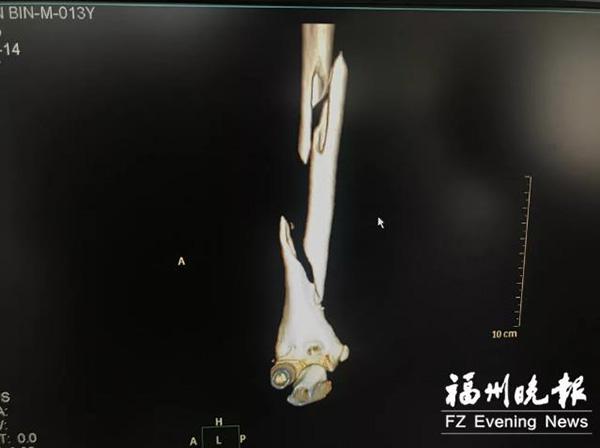

“送来我们医院的时候,他的右臂肿胀、畸形,局部明显压痛,活动受限,而且大拇指不会动了。”福州市二医院小儿骨科黄殿华医生介绍,片子显示,孩子“右肱骨干两处螺旋形骨折”“右桡神经损伤”,“也就是说,他的右上臂骨头断成了三节。”